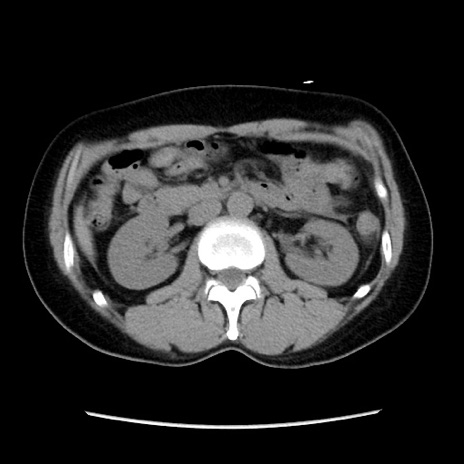

症例10(横断像)

【症例】 50歳代女性

【主訴】 腹痛

【現病歴】前日生レバーを食べた。今朝に排便あり。 昼前に突然発症の腹痛を生じ、当院救急外来を受診した。

【既往歴】 子宮筋腫にてで子宮全摘後

【身体所見】 意識清明、腹部:平坦、軟、下腹部やや左を中心に圧痛・反跳痛あり、筋性防御あり

【データ】WBC 7800、CRP 0.07